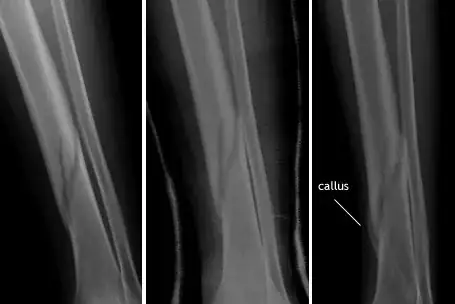

Note the callus is more easily seen in this series:

You can see the callus very clearly on week 9 when the leg was still in a cast; it is a rounded, radioopaque bulge adjacent to the fracture. The x-ray labelled "callus" was taken at 4 months.

Image of callus formation from Bone Growth and Remodeling